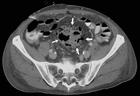

showed considerable free fluid, free air and a thickened wall of the sigma with multiple diverticula imposing as a pseudotumor without signs of an acute inflammation (Figure 2). This rose the suspicion of a traumatic sigma perforation. The left inguinal canal was fluid-filled with free air present (Figure 3). Because of the absence of an intensive care unit the patient was transported to a tertiary referral hospital for an urgent explorative laparotomy. The inspection showed a feculent 4-quadrant peritonitis with a perforation of the small bowel 50cm proximal to the ileocecal valve. The perforated small bowel was resected as a segment. A side-to-side ileostomy was formed. The sigma was indurated on palpation and suspicious of a colon cancer. In the intraoperative rectoscopy the tumor could not be reached. The inguinal canal was filled with stool and a lavage was performed together with the whole abdomen. A drainage was placed and the abdomen closed temporary with a negative-wound-pressure therapy (NWPT) system. The preoperatively started intravenous antibiotic treatment with imipenem was continued. On the first postoperative day, a rectosigmoidoscopy was unable to pass the stenosis in the sigma. A repeat CT of the abdomen with rectal and intravenous contrast showed wall thickening of the sigma with perifocal lymphadenopathy (Figure 4). In the 2nd look laparotomy 48 hours after the initial operation an anterior resection with complete mesocolic excision and partial mesorectal excision was performed because a malignant disease could not be excluded. A descendorectostomy was performed and the side-to-side ileostomy was reversed into a protective splitstoma. Again, the inguinal hernia was not touched due to the contamination. The NWPT was continued and after two NWPT changes primary fascial closure was achieved eleven days later. The histopathology showed a covered perforation of a sigma diverticulitis with inflamed pseudotumor without signs of malignancy. 22 days after the tennis accident the patient was discharged for rehabilitation. One month later he is in a good health condition and is waiting for the reversal of the stoma and definitive treatment of the inguinal hernia.